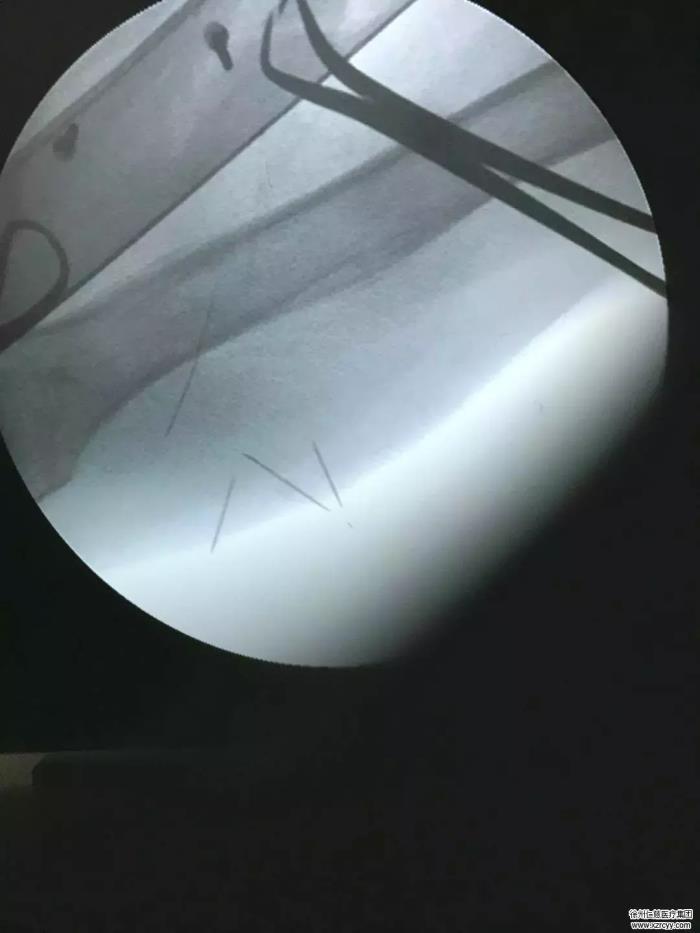

近日,南京一名女子为了备孕在一家诊所做针灸调理,起针时发现针灸的细针竟然断在了自己的腰里,为此女子2天跑了5家医院,做了2次手术才把它取出来。

此类金属异物取出术第一难就是定位困难。目前可用X 线、CT、超声、内镜等方法,但由于肌肉运动收缩,针很可能在刚做完检查与进手术室这个期间瞬时移位。

第二难就是操作困难。手术入路要选在金属针距皮肤最近,皮肤与金属针间无重要血管、神经等重要组织结构处。有的针已经扎进器官,伤口极容易发生感染,引起局部脓肿,甚至可能腐蚀附近的组织。